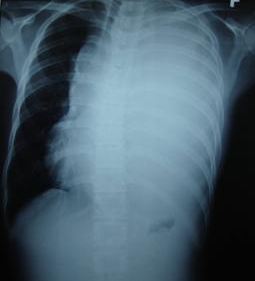

Sau đó bệnh nhân đã được điều trị hoá chất phác đồ VIP 04 đợt. Sau đợt điều trị hoá chất đầu tiên, khối u thành ngực thu nhỏ dần dần và sau 20 ngày truyền hoá chất tổn thương tại thành ngực đã tan (không nhìn thấy và không sờ thấy u bằng tay trên lâm sàng)

Trên phim chụp cắt lớp vi tính lồng ngực: Tổn thương u trung thất đã thu nhỏ kích thước hơn trước, phổi trái đỡ xẹp